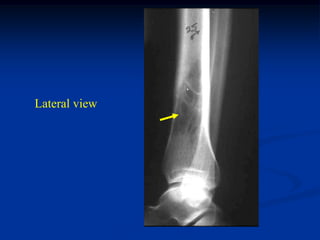

Case #420

3 year female

path fracture

EG femur

Lateral view